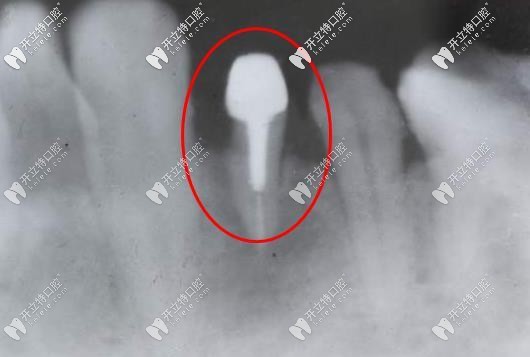

打樁后的牙片